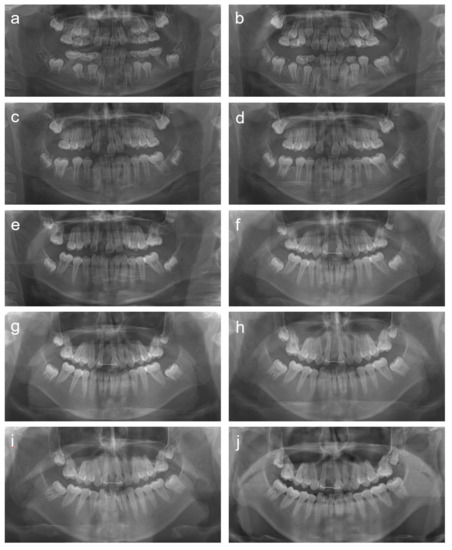

2. Cases

2.1. Case 1

2.2. Case 2

2.3. Case 3

2.4. Case 4

2.5. Case 5